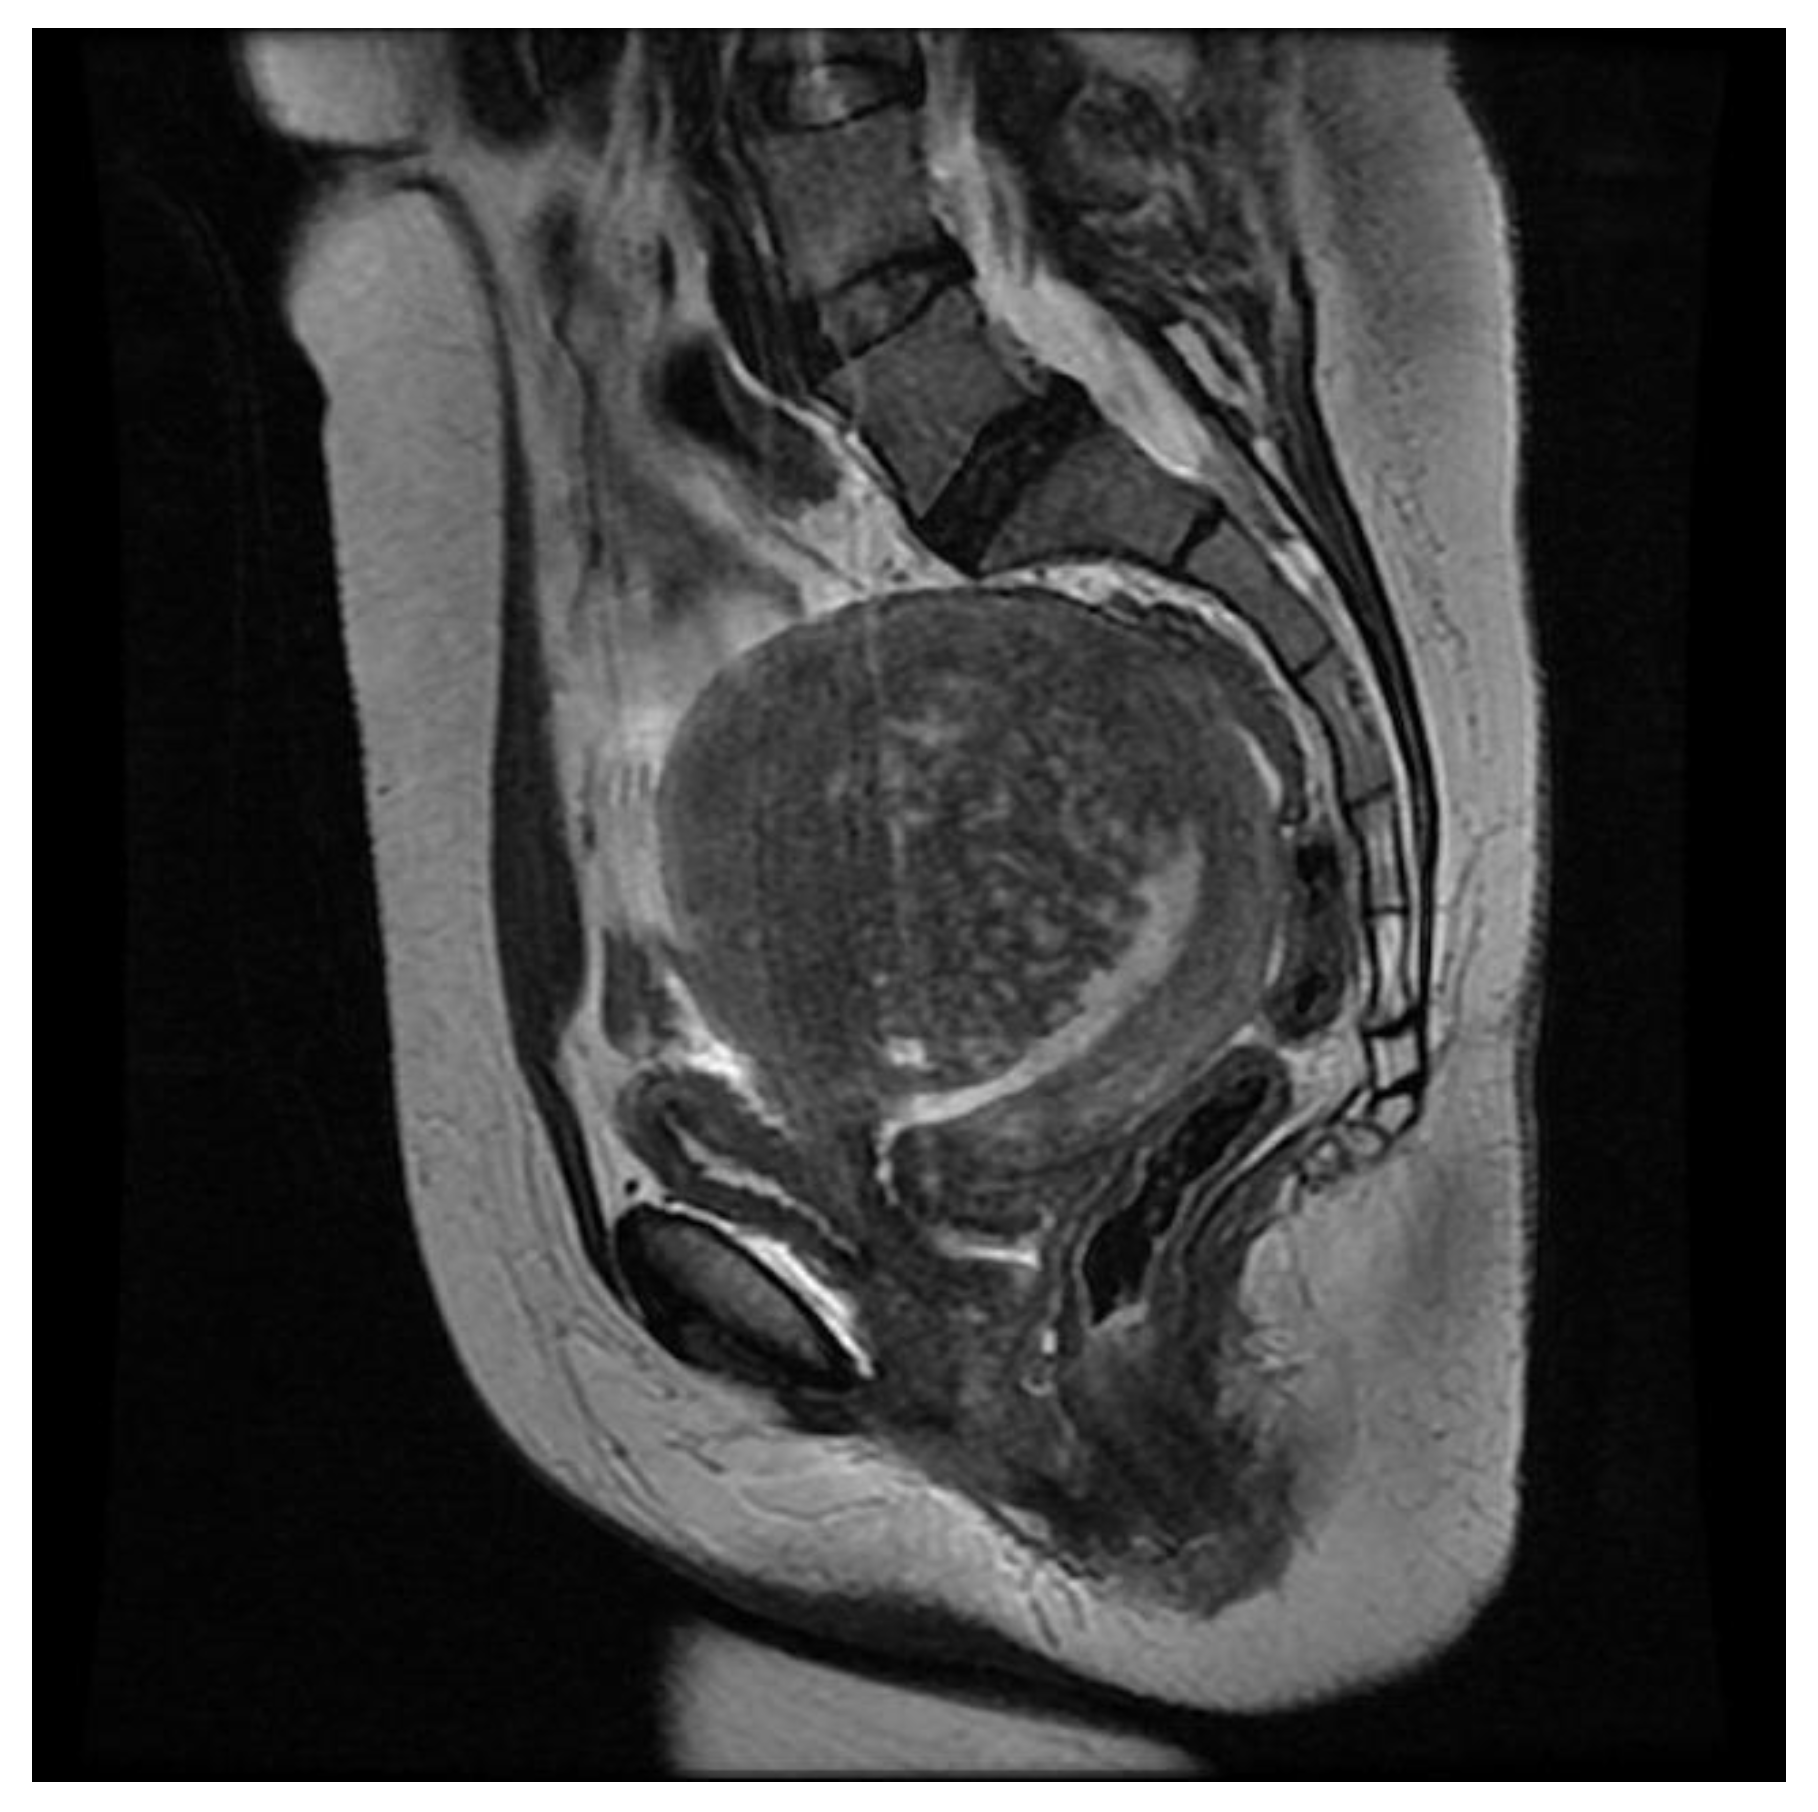

MRI and Adenomyosis: What Can Radiologists Evaluate?

3.3.1. Internal Adenomyosis

3.3.2. External Adenomyosis

3.3.3. Adenomyoma